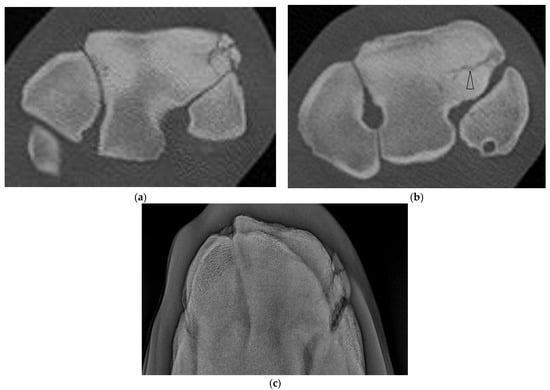

Horses ranged in age from 2 to 7 yr (mean 4.27 yr) for cases and 1 to 6 yr (mean 3.2 yr) for controls. Film radiographs (XR) were available for the fractured carpus of all 15 horses, and of the contralateral carpus in 6 horses. CT was available of the contralateral carpus of 13 horses. Fracture cases included 2 incomplete and 13 complete Fx, either frontal (n = 13) or corner (n = 2), and ranged from simple to severely comminuted. Signalment, Fx characteristics and other lesions are described in Supplementary Table S2. XR underestimated or failed to detect bone injury in all cases including comminution (nine horses) or an additional major fissure (one horse, Supplementary Figure S1), bone loss at the proximal articular surface (five horses), partial or full thickness subchondral bone lucency (SCBL) (four horses), medullary lucency in C3 (three horses) and radiocarpal bone (Cr) and or intermediate carpal bone (Ci) lesions (five horses) including osseous fragments (OF) and small, linear, triangular or rounded dorsal cortical lucencies (DCL). Incomplete C3 Fx was only detected on CT in three horses. CT confirmed Fx configuration as corner rather than sagittal in one horse. In another horse, CT identified Y- or saucer-shaped lucency within the RaF and InF of both carpi; an incomplete frontal Fx extended from the RaF lesion (Figure 1). CT confirmed complete Fx in 1 horse when incomplete Fx was diagnosed on XR. Bone injury was detected in the contralateral carpus in eight horses (8/13, 61.5%) including incomplete Fx RaF (two horses), SCBL within C3, Cr and or distal radius (diRd) (six horses) and OF Cr or Ci (three horses); and DCL were present in 2 horses.

Figure 1. CT images of the distal row of carpal bones of a 5-year-old thoroughbred gelding (post-mortem specimens). (a) Transverse CT image of the right carpus just below the proximal articular surface of the third carpal bone (C3), and (b) through the distal third of C3. (c) Dorsal CT image of the right carpus. There is a circular lucency within the radial facet (arrow head (a)) that extends as a Y-shaped lucency into the sclerotic medulla of C3 (arrow (c)), and an incomplete frontal fracture extending from this lesion to exit the dorsal cortex of C3 (a,b). Concurrent lesions include small dorsal cortical lucencies (arrows (a)) and a focal lucency within the distal subchondal bone of the intermediate facet (arrow head (c)). (d) Transverse CT image of the left carpus reveals similar circular lucencies within the radial and intermediate facets (arrows); the lucencies are saucer-shaped on dorsal and sagittal images (not shown).